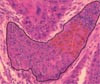

En strikt kvantitativ og reproduserbar beskrivelse av vevsarkitektur er fremdeles en utfordring i diagnostisk patologi. De mest lovende metodene er basert på såkalt grafteori. Gråtonebilder fra standard HE-fargede snitt overføres fra mikroskop via kamera til datamaskinen. Fra disse gråtonebildene identifiseres cellekjernene, og man ser bort fra annen informasjon i bildet. Det geometriske tyngdepunktet i hver cellekjerne beregnes, og slik genereres en todimensjonal punktsverm. Dette danner utgangspunktet for konstruksjon av ulike grafer, f.eks. Voronoi-diagrammet (fig 7) og Delaunay-trianguleringen (fig 8). Fra de mosaikkene som genereres (fig 9), kan man trekke ut ulike formparametere som gir en numerisk beskrivelse av vevsarkitekturen. Disse data kan benyttes til histologisk klassifikasjon, noe som blant annet er godt dokumentert i studier av lungevev (84, 85).

Vi har blant annet anvendt slike grafteoribaserte modeller i en pilotstudie på lokalisert prostatakreft, 15 pasienter med god og 15 med dårlig prognose. Alle pasientene var behandlet med radikal prostatektomi uten komplikasjoner. Som god prognose ble angitt overlevelse mer enn ti år, og gruppen med dårlig prognose hadde mindre enn fem års overlevelse. Som figur 10 viser, kunne vi i denne pilotstudien klart skille mellom prøver fra pasienter med henholdsvis god og dårlig prognose. Hvis disse resultatene kan bekreftes i en full studie (under arbeid), har vi nok en prognostisk metode for pasienter med prostatakreft.